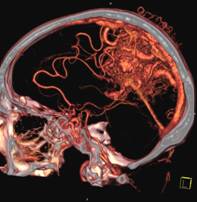

头颅一站式检查:320排容积CT覆盖范围达16cm,球管旋转一周可以覆盖整个脑组织,获得全脑0.5mm层厚各向同性全脑信息。一次扫描可以获得平扫容积图像、以时间为序列全脑动态3D-CTA图像(包括纯动、静脉期成像)及全脑灌注图像。一次检查即可排除脑出血、动脉瘤、动脉狭窄、梗塞、脑实质供血异常等多种病变及进行脑卒中筛查。

脑血管畸形CTA ,大血管成像:动态容积成像实现大范围动态血管检查